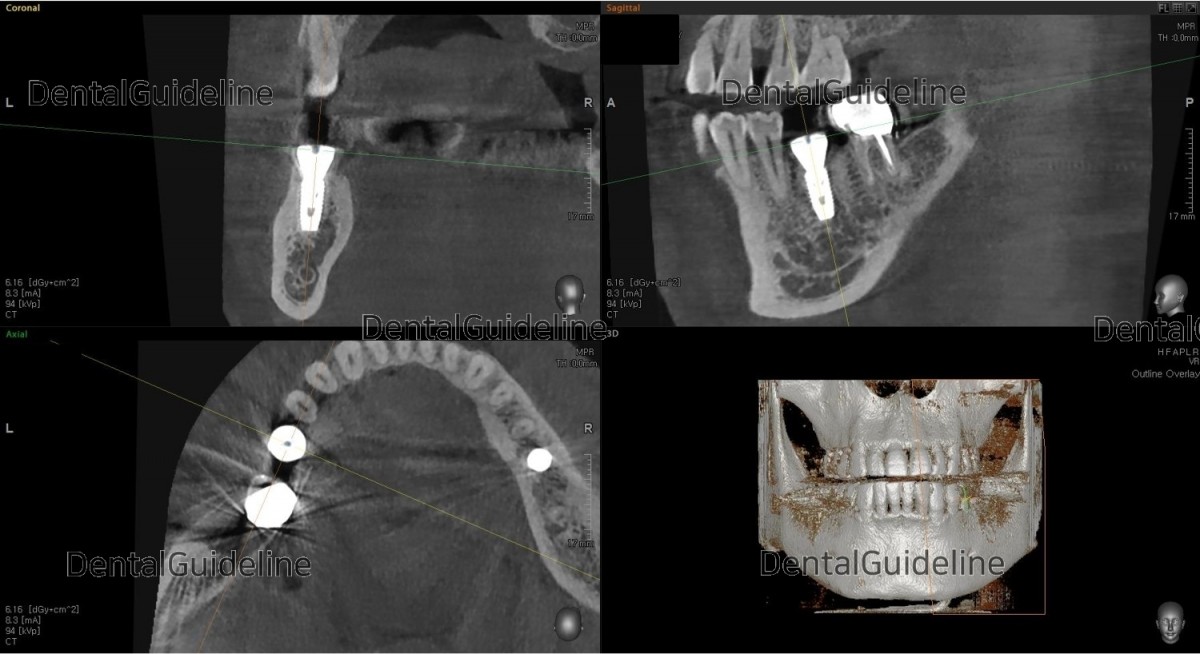

CBCT scanning image focused on the 1st molar

extraction

CBCT scan image after placement of the implant.